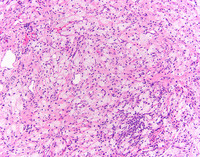

Low power H&E

Punch biopsy show diffuse dermal infltrate of bland cells with pale cytoplasm.

At higher power, foamy histocytes with bland nuclear morphology occurring singly and in aggregates are noted. These cells are characterized by vacuolated cytoplasm,  often in a fibrotic background with admixed chronic inflammation.